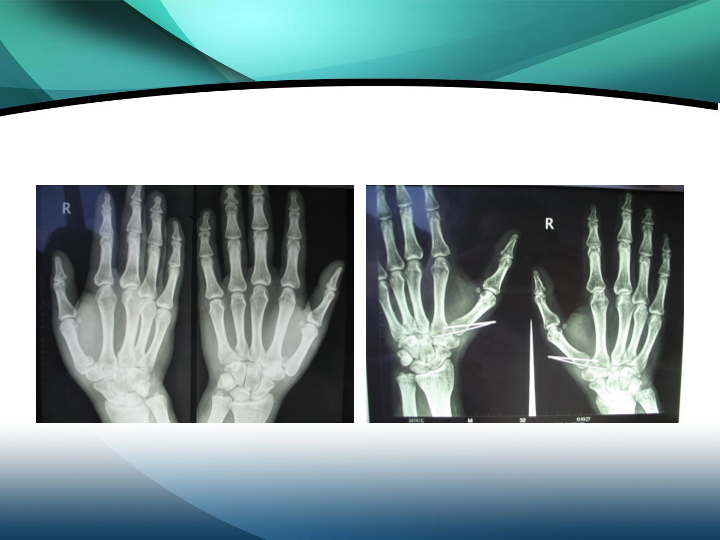

掌骨骨折